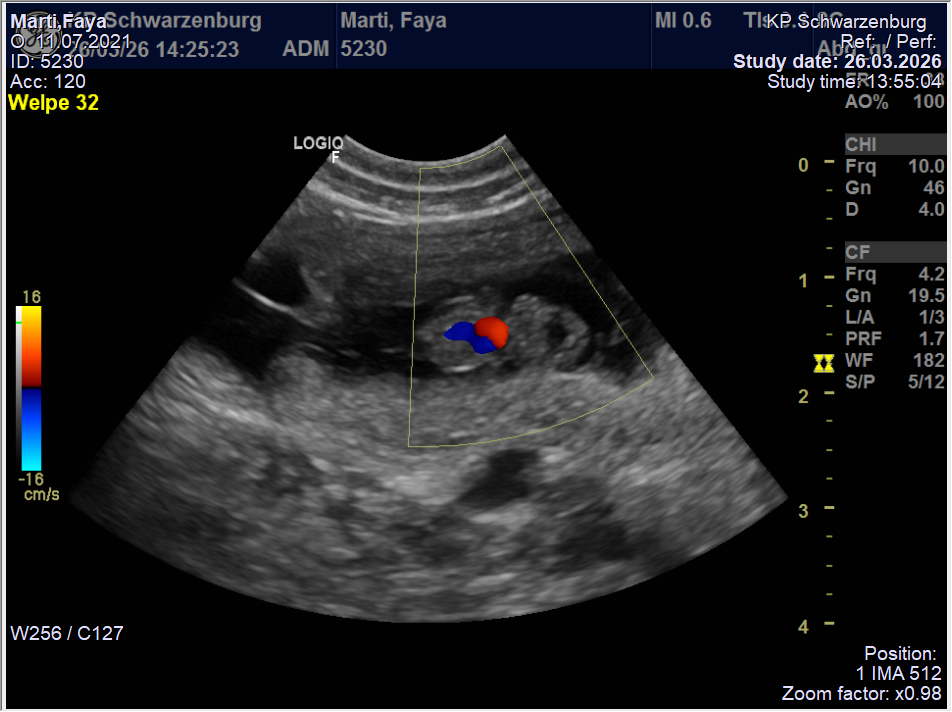

Nun heisst es weiter „brüten“ bis die Welpen Ende April auf die Welt kommen…